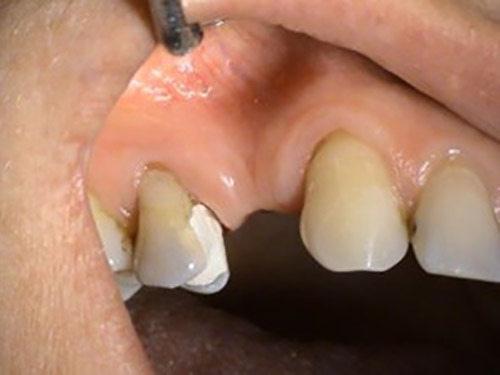

3. PHASE – fabrication of temporary solution